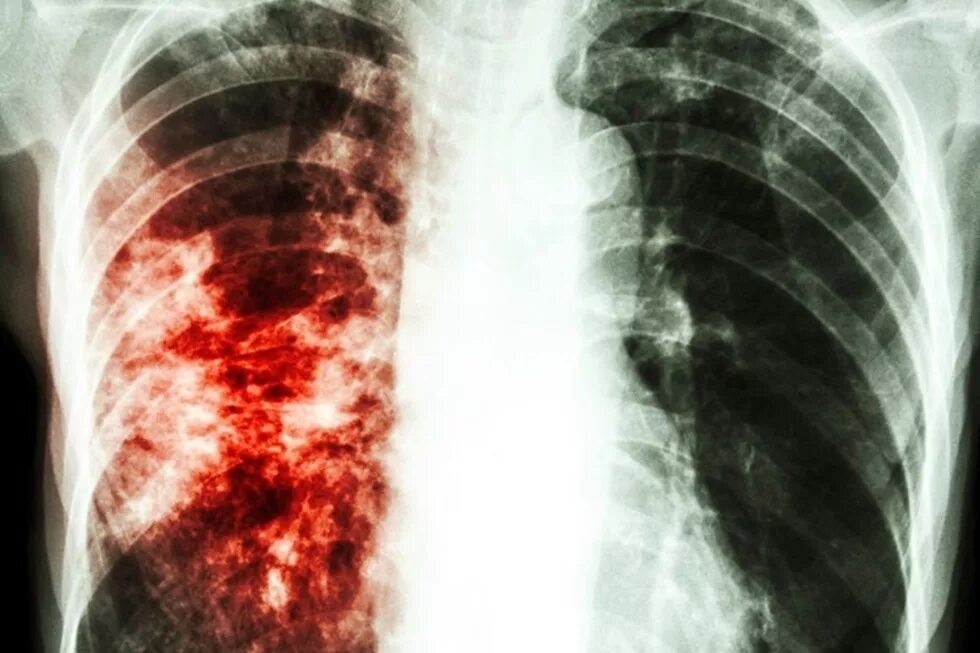

Поражение легких при туберкулезе